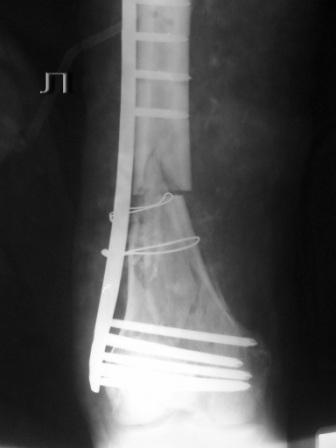

Пациенту 50 лет. 24.11.09 сделали л\бедро.

Оставлен клинически значимый варус, видно градусов 8-10. Для уточнения можно сделать снимок симметричного сегмента и скиаграммы наложить.

Не стоило открывать промежуточные отломки и вязать их проволокой. Это ухудшает их кровоснабжение и может привести к несращению. Не во все случаях, конечно. Удачи.

Сложность репозиции привела к "освобождению" промежуточных отломков - появился значительный костный дефект - пришлось создавать картинку + добавили коллапан.

Не удивляйтесь, если пластина сломается(((

Какова возможная причина перелома импланта, ведь принцып "мостовидности" пластины LCP соблюден!?

Мостовидность это только часть , так называемого, биологического принципа.Биологический принцип предполагает баланс между механическими свойствами остеосинтеза и сохранением кровоснабжения кости и окружающих мякких тканей. Мостовидная фиксация обеспечивает относительную, эластичную стабильность, которая при малоинвазивной технике (MIPO), т.е, при закрытой репозиции и нескелетировании кости дает хороший шанс на быстрое течение репаративных процессов и сращение перелома.

В Вашем примере, как мне кажется, была довольно травматичная открытая реползиция со скелетированием концов перелома. В результате отсутствует необходимая биологическая составляющая для нормальной репарации кости. кроме того, положение отломков по оси - так себе, и имеется значимый медиалный дефект. Так что к био-логической мостовидной технике фиксации переломов этот случай не имеет никакого отношения. Увы(